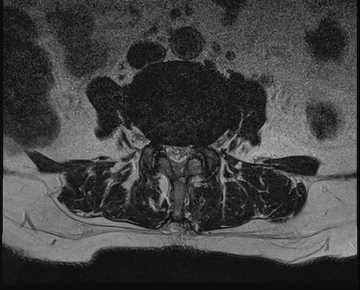

요추 협착증 수술 전·후

2020.08.30

2022.09.06

ㆍ환자 동의를 받은 자료이며, 이미지 사진은 실물과 다를 수 있습니다.

ㆍ모든 자료는 새움병원 자료입니다.